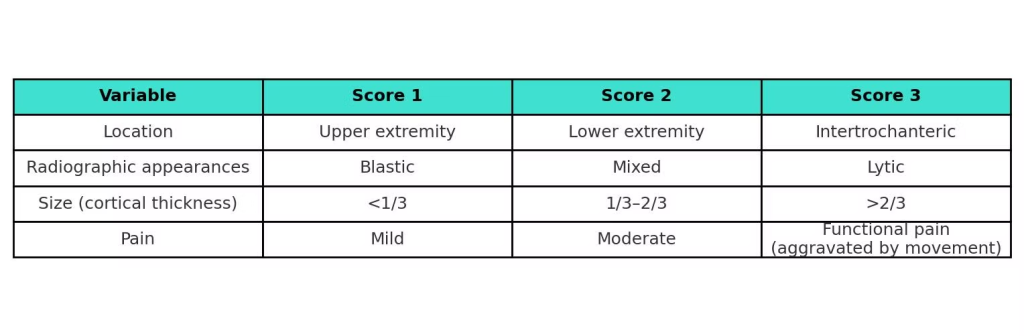

Prognosis & Decision-Making